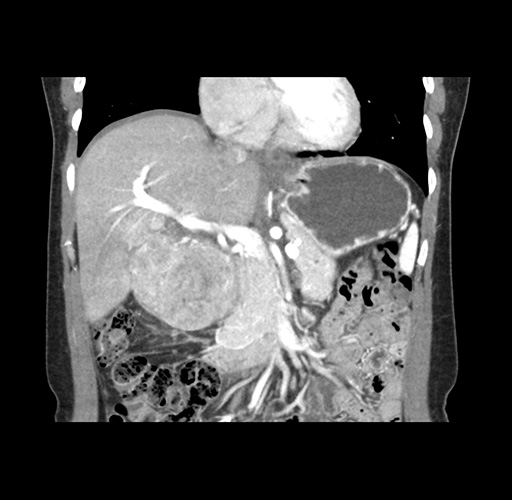

Imaging Analysis

Look through the patient's CT scan to identify any areas of concern for the necessary procedure.

Based on your CT findings, which issue(s) would give reason for "planned slowing down moment(s)" in this case?

Considering a standard left lateral sectionectomy procedure, what step(s) of the operation would you do differently in this case ?